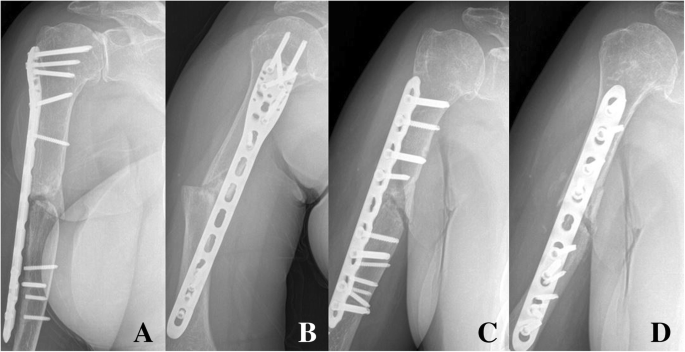

Классификация переломов диафиза бедренной кости: Иллюстрации и информация